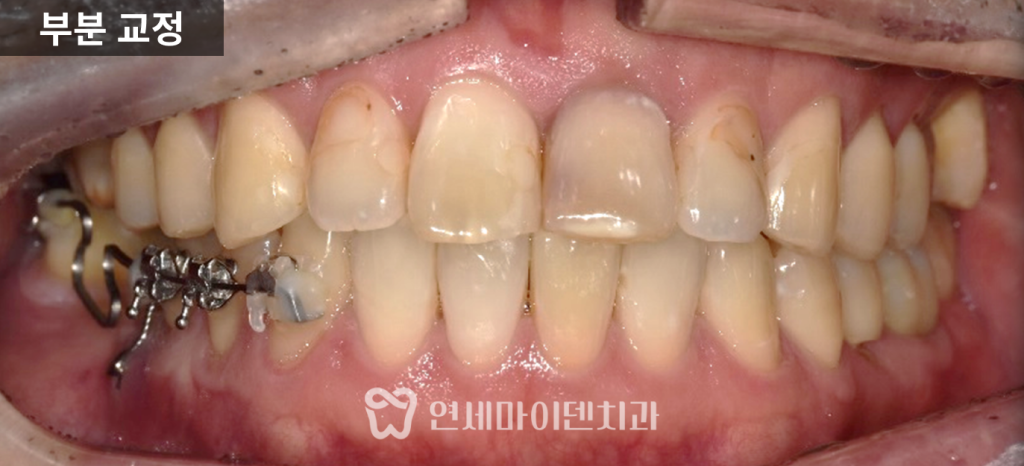

부분교정·임플란트 협진 증례: 쓰러진 어금니

실제 치료 사례를 바탕으로 작성되었습니다.안녕하세요, 소중한 치아를 지키는

연세마이덴치과 닥터꼬집입니다.“임플란트 해야 하는데

치아가 쓰러져서 공간이 부족해요.”임플란트를 계획하고 내원하신 분들 중

의외로 많이 듣는 말입니다.치아가 빠진 상태로 오랜 시간이 지나면

그 자리를 가만히 두지 않습니다.주변 치아들은 서서히

그 공간 쪽으로 기울고, 쓰러지고, 내려옵니다.이렇게 되면

치아교정·임플란트 협진 케이스를 설명드리겠습니다.초진 상태

초진 파노라마 사진에서

오래전 6번 어금니가 발치된 상태였습니다.그 뒤쪽에 있던 7번, 그리고 사랑니가

앞쪽으로 상당히 많이 쓰러져 있었습니다.

원래 6번과 7번은

크기가 거의 비슷해야 하는데,쓰러지면서

임플란트가 들어가야 할 공간이

앞 치아보다도 더 좁아진 상태였습니다.이 상태에서 임플란트를 바로 진행하면

부분교정으로 접근했습니다.부분교정의 핵심: 고정원 설계

부분교정에서 가장 중요한 것은

움직일 치아만 움직이고

나머지 치아는 최대한 고정하는 것입니다.

이 환자분은 과거 교정 이력이 있어

앞니 안쪽에 유지장치가 남아 있었고,

이 장치가 고정원 역할을 해주었습니다.여기에 미니스크류를 추가해

고정원을 더욱 보강했습니다.